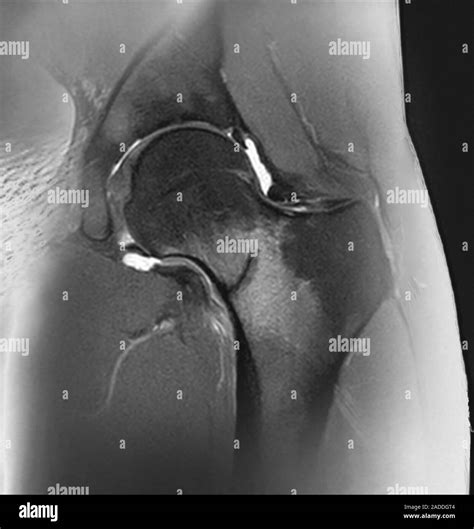

• MRI (Magnetic Resonance Imaging): This is the gold standard for diagnosing a stress fracture. It is highly sensitive and can detect bone marrow edema, which is the earliest sign of stress-related bone injury.